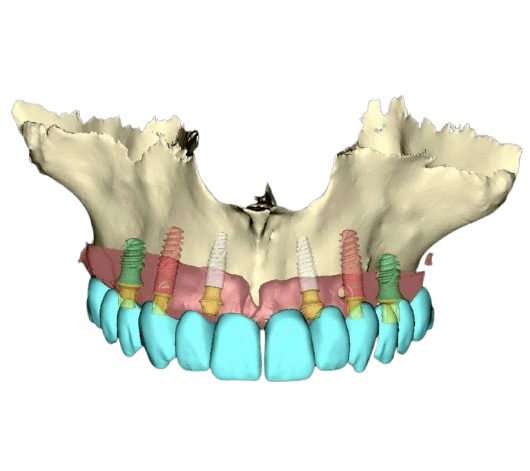

Die periimplantäre Chirurgie befasst sich mit dem Erhalt und der Wiederherstellung von Knochen und Weichgewebe um Implantate herum. In unserer Praxis setzen wir auf prothetisch geführte Planung und Implantation, um eine optimale Positionierung des Implantats – sowohl funktionell als auch ästhetisch – zu gewährleisten.

Vor oder nach der Implantation treten häufig Knochen- und Weichgewebedefizite auf, die horizontale oder vertikale Knochendefekte oder unzureichend festes, keratinisiertes Zahnfleisch sein können. Diese Defizite können die Langzeitstabilität und das ästhetische Ergebnis des Implantats erheblich beeinträchtigen.

Ist eine zahnärztliche Versorgung nach FP1-Standard nicht möglich und kann horizontaler oder vertikaler Knochenverlust nicht ausgeglichen werden, kommen alternative Methoden zum Einsatz. Bei mäßigem Knochenverlust und massivem Weichgewebsverlust – oder wenn der Patient aus Zeitgründen, finanziellen Erwägungen oder aufgrund von Angst keine Knochen- und Weichgewebsaugmentation wünscht – stellt die Versorgung nach FP2-Standard die ideale Lösung dar. Hierbei wird rosafarbene Keramik verwendet, die das fehlende Weichgewebe ästhetisch ersetzt und gleichzeitig ein stabiles und dauerhaftes Ergebnis gewährleistet.

Bei einem größeren Knochen- und Weichteildefekt ersetzen wir im Rahmen des festsitzenden Zahnersatzes 3 sowohl den Knochen als auch das Zahnfleisch durch die Zahnprothese (entweder Zirkon- oder Kunststoffprothesen - mit individuell ausgewählten Zähnen aus einem hochwertigen Premium-Set und einer Zahnfleischimitation, zum Beispiel aus Gradia-Material).